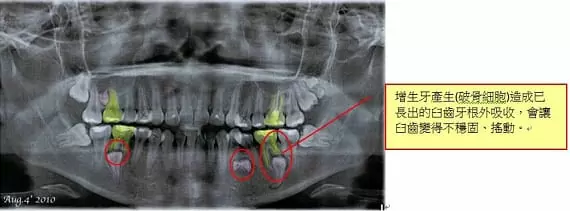

經曾醫師透過X光片診斷發現病症,病人屬於罕見的增生牙病況,(增生牙會導致正常成人牙齒的牙根產生破骨細包,而使牙根產生外吸收現象,病患到了約40多歲左右會因牙根的外吸收,造成牙齒不穩固、搖動的現象。

圖1.轉口腔外科將埋在骨頭裏的增生牙取出,並拔掉已產生牙根外吸收的牙齒及其他已長出的增生牙。